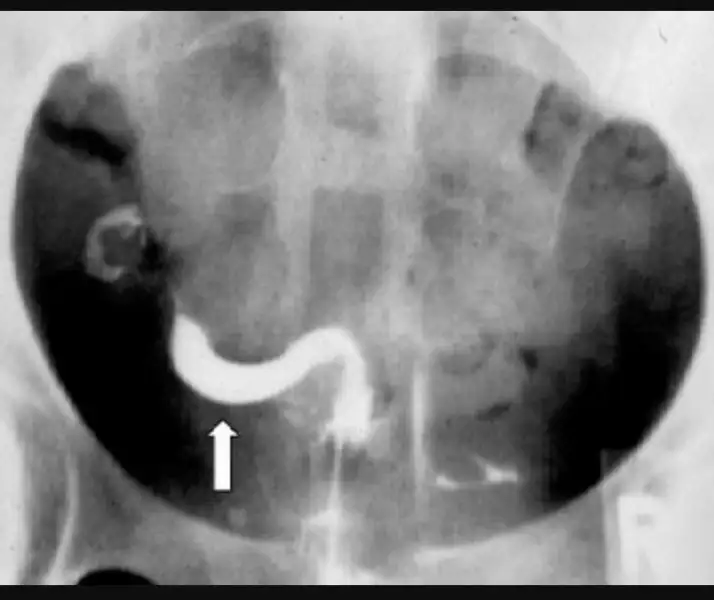

Yok cnm sen evham yapma herşey normal Dr Demiş işte.sadece rahmin geriye doğru yatık gibi duruyor yani Bayağı yatmış sanırım işte buna ters rahim deniyor ters rahim gebe kalmaya engel bir durum değil.

Aslında benimkini görseniz ters rahim nasıl olur anlardiniz bilgisayar olsa atacam size ama yok ki